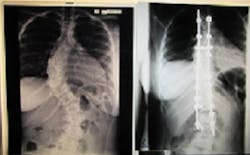

Three years ago, Sharena became the first young adult from the island of Dominica to benefit from scoliosis correction through a posterior spinal fusion. This surgery was provided to Sharena through World Pediatric Project (WPP), and supported through your donations to Globus Relief. World Pediatric Project works in Belize, Dominican Republic, Guatemala, Honduras, St. Vincent and the Grenadines, Panama, and in the Eastern Caribbean islands. Their mission is “to heal critically ill children and build healthcare capacity in the world.”